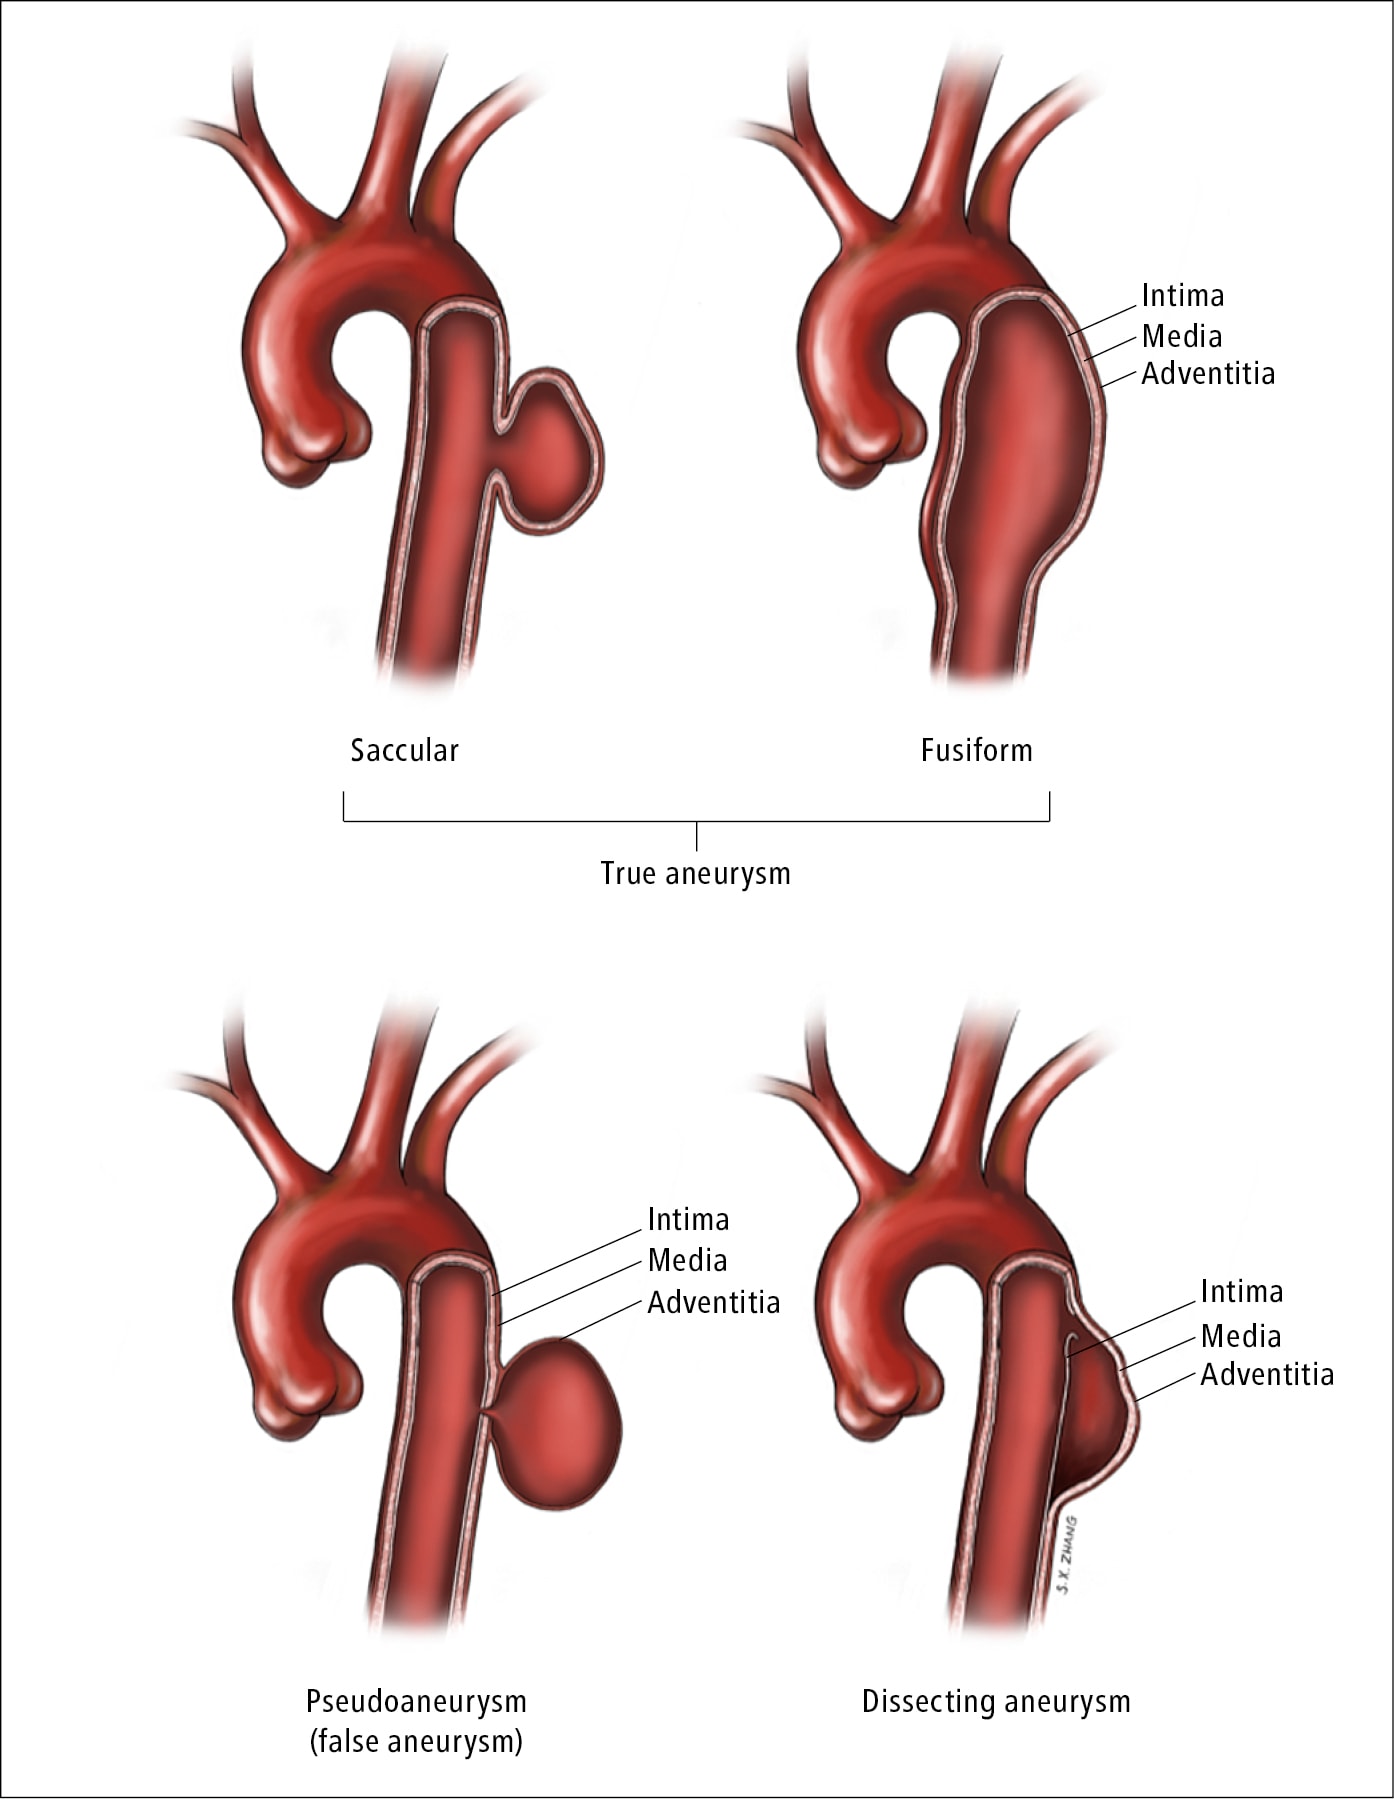

Aortopathy Cardio Guide

https://www.cardioguide.ca/wp-content/uploads/2021/06/Different-types-of-aortic-aneurysm.jpg

Aortopathy Cardio Guide